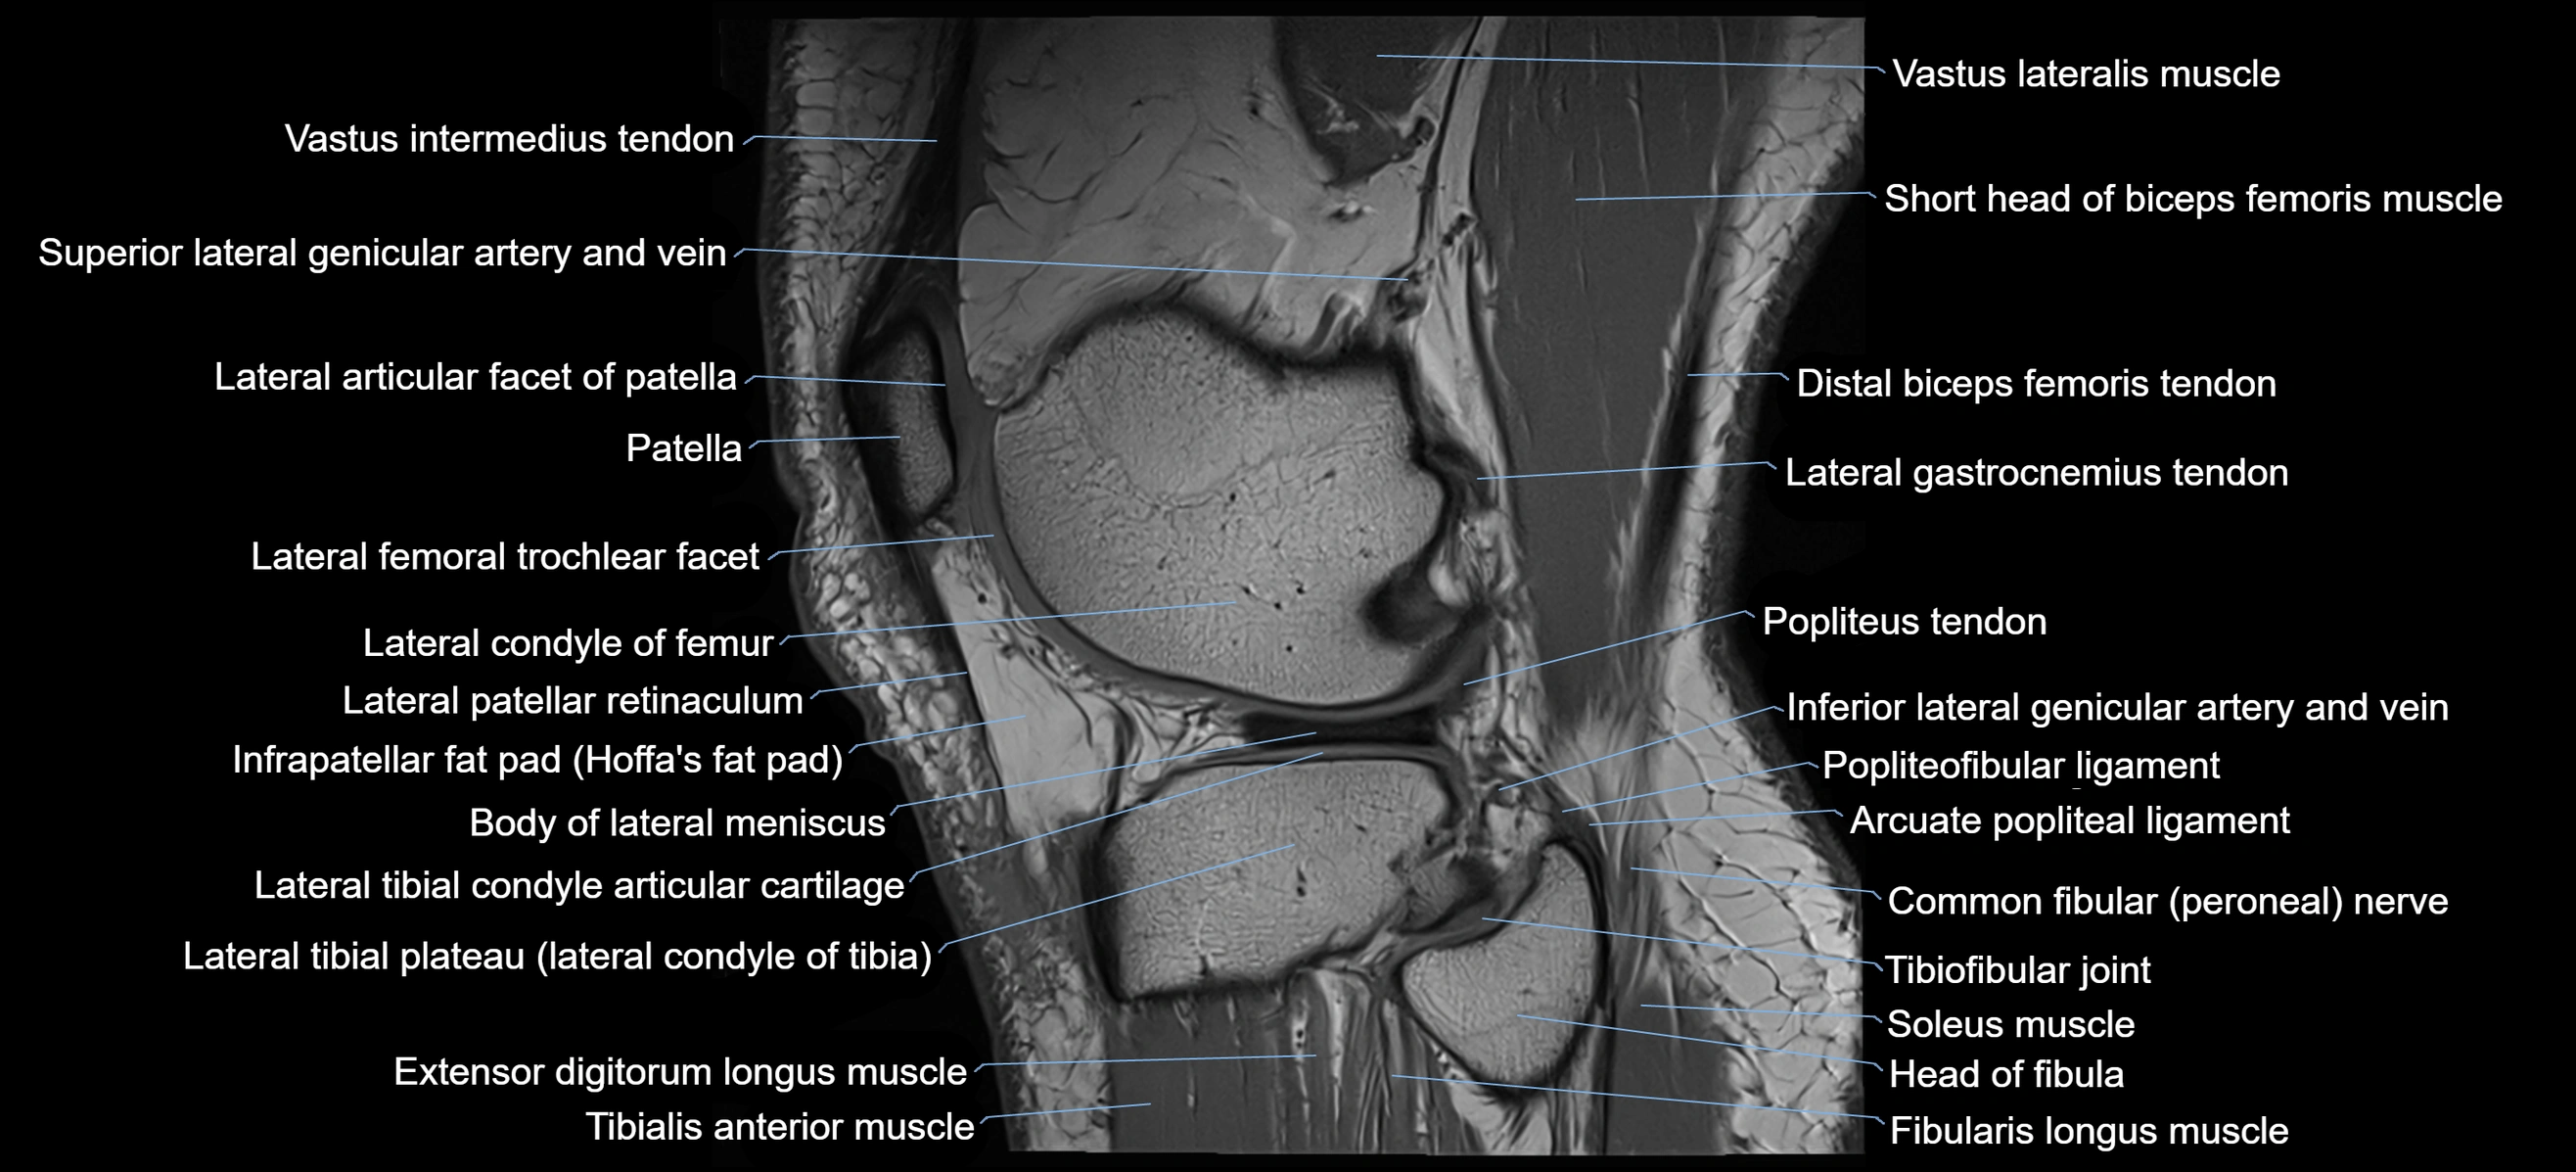

- Body of lateral meniscus

- Distal biceps femoris tendon

- Extensor digitorum longus muscle

- Fibularis longus muscle (peroneus longus muscle)

- Head of fibula

- Inferior lateral genicular artery

- Inferior lateral genicular vein

- Lateral articular facet of patella

- Lateral condyle of femur

- Lateral gastrocnemius tendon

- Lateral head of gastrocnemius muscle

- Lateral patellar retinaculum

- Lateral tibial plateau

- Popliteus tendon

- Soleus muscle

- Superior lateral genicular artery

- Superior tibiofibular joint

- Tibialis anterior muscle

- Tibiofibular joint (proximal)

- Vastus lateralis muscle